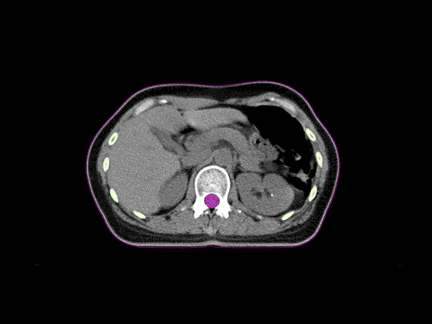

CT-IGRT de înaltă calitate

Tehnologia CT-IGRT (Image-Guided Radiotherapy bazată pe tomografie computerizată) oferă imagini de precizie diagnostică pentru ghidarea tratamentului în timp real. Aceasta permite localizarea exactă a tumorilor, monitorizarea mișcărilor pacientului și ajustarea dozei cu acuratețe milimetrică, contribuind la eficiența și siguranța maximă a radioterapiei.

Imagistică CT superioară

Câmpul vizual (FOV) extins și lungimea mare de scanare oferă flexibilitatea clinică necesară pentru o planificare precisă a radioterapiei. Această performanță îmbunătățită a imagisticii CT permite obținerea de detalii anatomice clare, esențiale pentru localizarea exactă a tumorilor și administrarea controlată a dozei de radiație.

Calcul al dozei la standard de aur

Acuratețea densității electronice obținută prin tomografia computerizată cu fascicul conic (FBCT) oferă o bază solidă pentru calculul precis al dozei de radiație. Această precizie este esențială pentru planificarea tratamentelor personalizate, asigurând o distribuție optimă a radiației și protejarea eficientă a țesuturilor sănătoase.